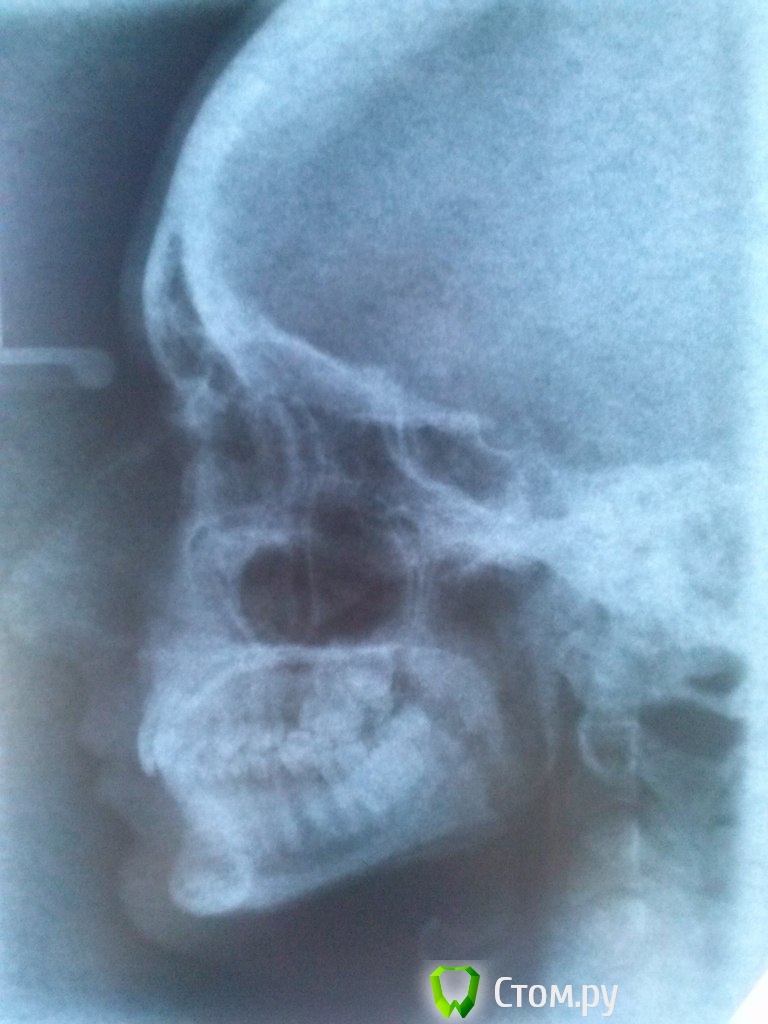

makemake Опубликовано 13 октября, 2014 Автор Поделиться Опубликовано 13 октября, 2014 Синус-лифтинг ведь не всегда удачен? Я бы оставила все как есть,но у меня асимметрия (я думаю это видно даже по оптг)верхняя челюсть в сторону ушла(по снимку это будет слева)Вроде как это крен верхней челюсти называется. Я просо боюсь,если выдрать 8ку еще с той стороны,то асимметрия будет еще хуже( глаз станет ниже)попробую сделать фото,наверное по описанию и оптг все же сложно понять, Ссылка на комментарий

M@estro Опубликовано 27 октября, 2014 Поделиться Опубликовано 27 октября, 2014 Гипертонус жевательных мышц справа . Причина асимметрии не в отсутствии зуба. Нужен ортодонт,который свободно работает с суставными и мышечными дисфункциями,владеет артикулятором и сплинтами ( шинами). 2 Ссылка на комментарий

makemake Опубликовано 28 октября, 2014 Автор Поделиться Опубликовано 28 октября, 2014 (изменено) Гипертонус жевательных мышц справа . Причина асимметрии не в отсутствии зуба. Нужен ортодонт,который свободно работает с суставными и мышечными дисфункциями,владеет артикулятором и сплинтами ( шинами).Именно по этому у меня справа есть ощущения,что мыщцы "тянет",а левая сторона больше по объему? Я думала,что мыщцы как раз в тонусе слева,где все зубы на месте Мне предлагали шину,но когда сказали,что скорее всего нужно будет подпиливать зубы и "может быть в процессе лечения вам понадобится протезирование и коронки" (у меня свои зубы в порядке!), я оттуда убежала. Или это реально,что протезирование вдруг будет нужно?Получается,что брекеты мне не нужны? Или нужны будут уже после шины? PS:может кто знает,есть такие специалисты в Новосибирске\Барнауле? Изменено 28 октября, 2014 пользователем makemake Ссылка на комментарий

makemake Опубликовано 29 октября, 2014 Автор Поделиться Опубликовано 29 октября, 2014 PS мамочки,почитала соседнюю тему http://forum.stom.ru/topic/25979-problema-s-cheliustiu-pomogite/там похожие симптомы. Я теперь и вовсе боюсь что-то "пилить". Подскажите пожалуйста,что в моем случае ТОЧНО не должен делать врач,чтобы я знала,когда на консультации ходить буду.И какие снимки и обследования НУЖНО сделатьТак болит правая сторона головы,что-то невоорбразимое. Мне страшно наделать еще хуже,чем сейчас есть. Но и не делать нельзя.Еще пол года назад сустав хрустел,а теперь перестал,за то гипертонус мыщц стал еще сильнее. Голову тянуть стало к плечу тоже сильнее,и если ее опускать,то неприятные ощущения в правой стороне меньше. Неужели из-за проблем со спиной такое ? Ссылка на комментарий